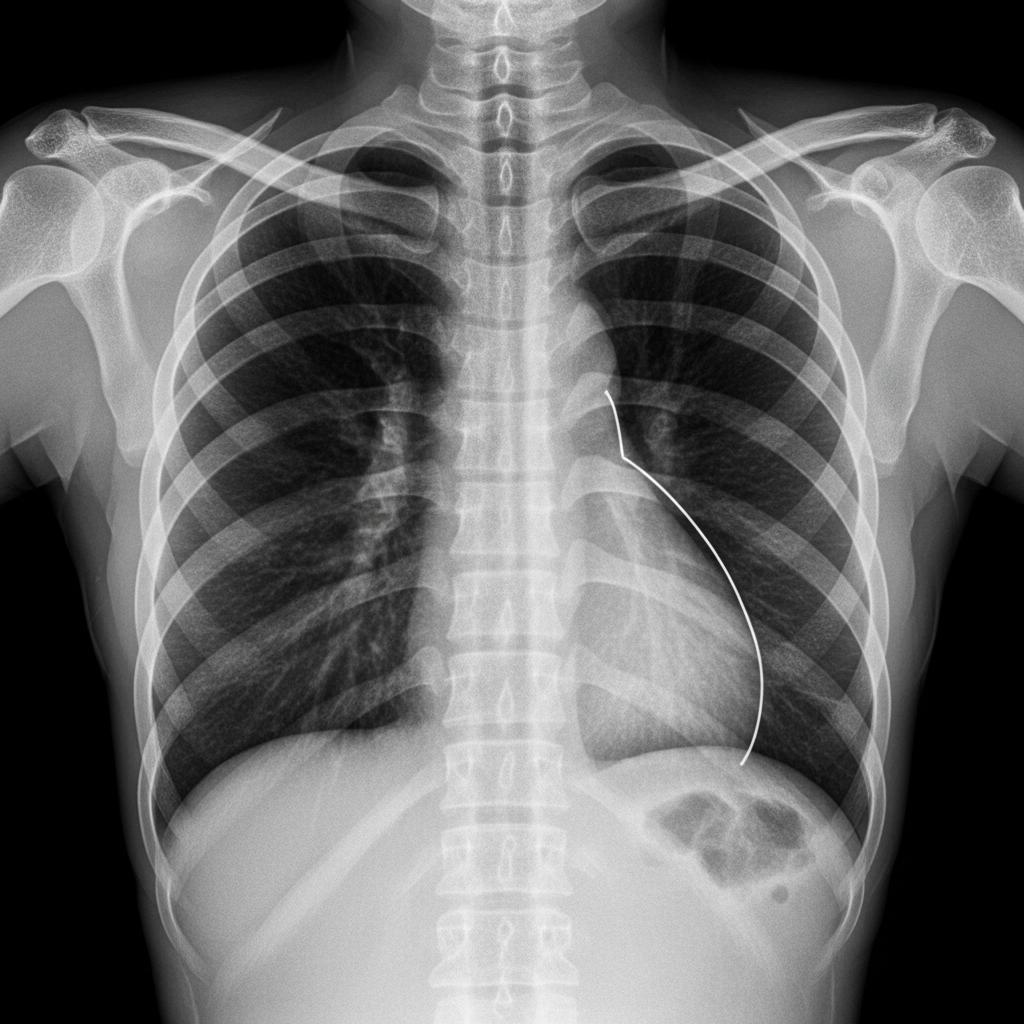

3. Natychmiastowe skierowanie na RTG klatki piersiowej – to podstawa rozpoznania, pozwala zobaczyć obecność powietrza w jamie opłucnej.

Obrazowanie: rentgen, tomografia i inne narzędzia XXI wieku

Diagnostyka obrazowa to „złoty standard” w rozpoznawaniu odmy. Najczęściej wykorzystuje się klasyczne zdjęcie rentgenowskie, które w 90% przypadków pozwala postawić prawidłową diagnozę. W przypadkach wątpliwych lub przy podejrzeniu odmy złożonej, wykonuje się tomografię komputerową.

Prześwietlenie klatki piersiowej z charakterystycznymi objawami odmy opłucnowej, sprzęt szpitalny, słowa kluczowe: odma opłucnowa, diagnostyka, rentgen

Nowoczesne szpitale korzystają też z ultrasonografii jako narzędzia przesiewowego przy urazach klatki piersiowej – szybko, bezpiecznie i bez promieniowania.